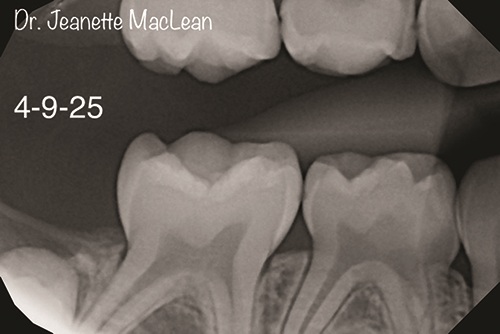

Figs. 2a and 2b: Overjet identifies incipient caries lesions, highlighted in yellow. Surgical intervention is not indicated at this time. Nonsurgical treatment with silver diamine fluoride is offered and accepted by parent.

Figs. 4a and 4b: Overjet confirms the incipient lesions are stable after treatment with silver diamine fluoride (Advantage Arrest, Elevate Oral Care). The lesions between the mandibular right primary molars are no longer detectable.

A four-year-old patient presents with his mother for a second opinion exam. The mother of the child expresses concern for a surgical treatment plan presented by another pediatric dentist, since her child has no visible decay and is asymptomatic. Patient’s aunt, a dental hygienist who lives out of state, suggests they see me for a second opinion to determine whether a less invasive approach could be taken. The child’s mother had never heard of silver diamine fluoride but was extremely grateful for the nonsurgical option and agreed to have it applied the same day. Patient returns five months later, six months since his last prophy at the previous provider. New bite wings show that the incipient lesions are stable, and SDF is reapplied. Patient’s little sister is also seen for a new patient exam. Both parents attend this visit and express their extreme gratitude for the noninvasive treatment option I gave them, and state that they have been telling their friends with children about their experience.